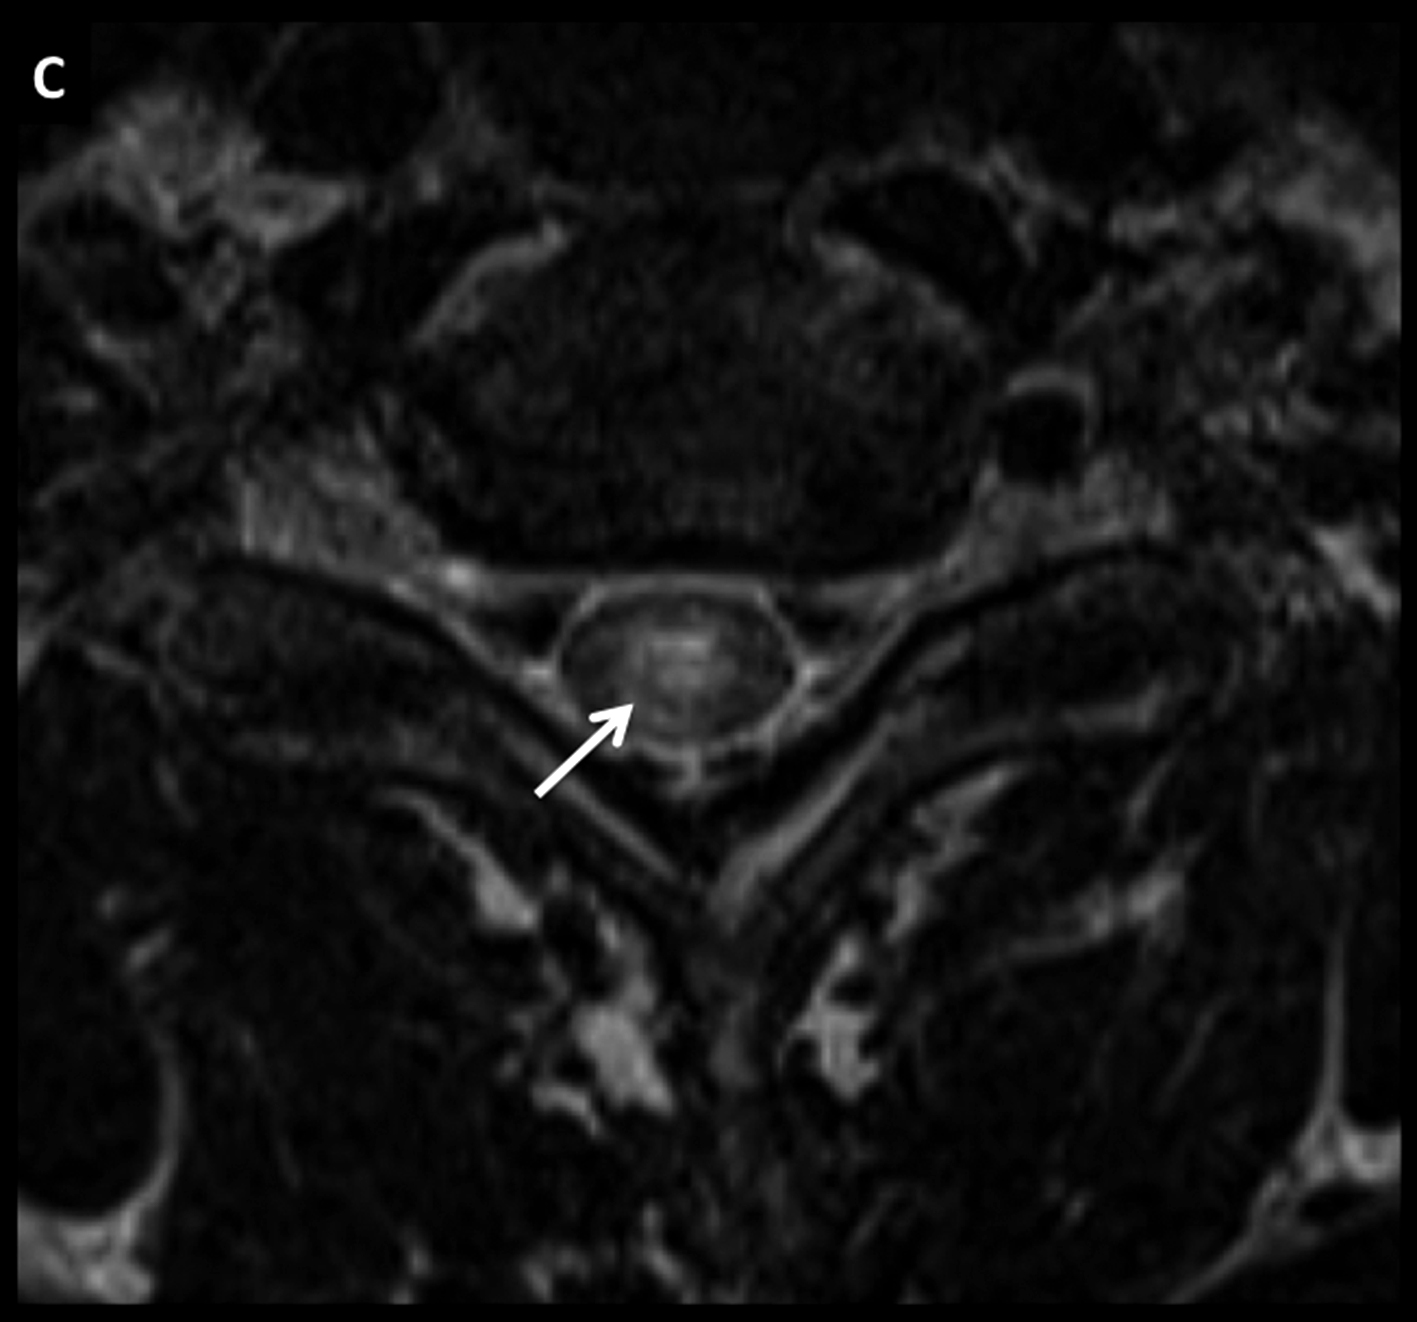

Figura 7

LNH, infiltración de cola de caballo, compromiso leptomeníngeo secundario.

Paciente joven con LNH y síndrome radicular asociado. En el estudio de estadificación se encuentra un patrón de infiltración de las raíces de la cola de caballo y se confirma el diagnóstico por estudio citológico del líquido céfalo raquídeo.

Este tipo de patrón se caracteriza por raíces nerviosas engrosadas que luego de administrar medio de contraste (D a F) presentan intenso realce.

El proceso infiltrativo rodea al cono medular (flecha discontínua) y puede contribuir a la clínica del paciente.